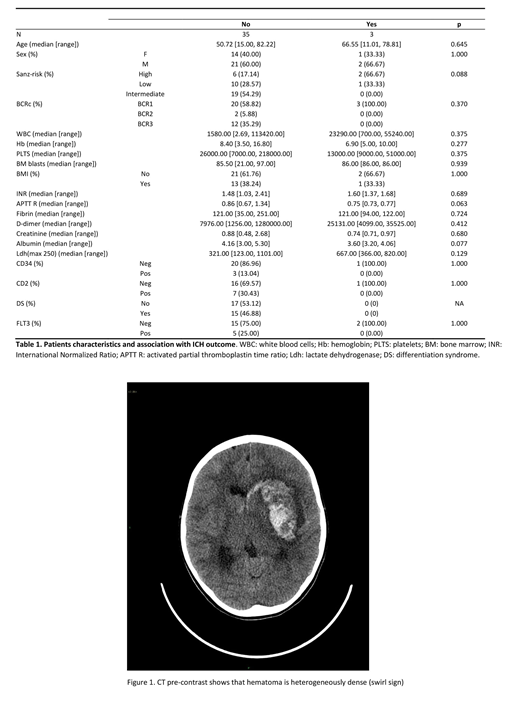

Approximately 13% (5/38) of our APL patients experienced an ICH during induction therapy, which was fatal in 3 cases, while the overall incidence of ED was about 10% (4/38, including 1 case of death due to a differentiation syndrome). Looking at clinico-biological variables, the only predictor of ICH was a lower albumin level at baseline (3.8 vs 4.2 gr/dl; p=0.022), as compared to patients who did not experience ICH. A high Sanz-risk score was present in 2 of 3 pts with a fatal outcome of ICH (67% of cases), together with a shorter activated partial thromboplastin time (aPTT, 0.75 vs 0.86 ratio)(Table 1). Looking at neuroradiological findings (Figure 1) the three fatal cases showed a wider ICH volume, with perilesional edema and, interestingly, a positive "swirl" sign, which is defined as a marker of ongoing extravasation of blood within a hematoma. Both cases with a favourable outcome had a cerebellar involvement, without perilesional edema, and no major involvement of basal ganglia or thalamus. None of the patients had radiological signs of arteriovenous malformations.

Our data remark the impact of lower albumin levels at baseline and of a high Sanz-risk category on ED in patients with APL. In APL cases with fatal ICH, the thrombo-hemorrhagic imbalance is more profound than in other AMLs and results in a more devastating clinical picture. Taking into account the limitations of the small sample size, we found that a wide hemorrhage volume with perilesional edema, and the presence of the "swirl" sign are characteristic of fatal cases, while arteriovenous malformations did not seem to play a predisposing role. Further studies including large series of patients are warranted to identify the characteristics and the possible strategies to ameliorate the outcome of ICH in APL.